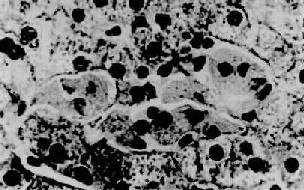

高雪(Gaucher)病,也称脑苷脂沉积症,是由于常染色体隐性遗传所致体内β-葡萄糖苷酶缺乏而引起的脑苷脂分解代谢障碍。主要累及肝、脾、淋巴结及骨髓等单核吞噬细胞系统。常发生在婴儿,为致命性疾病。主要病变为肝、脾肿大,脾大尤为明显,可达正常脾重的20倍。镜下,肝内聚集大量高度胀大的载脂巨噬细胞,有的胞浆呈泡沫状,有的胞浆出现红染条纹,后者排列成皱纹纸样外观,胞核小,圆形或椭圆形居于细胞中央,称为高雪细胞(图10-33)。这些细胞主要分布于小叶中央静脉附近的肝窦内和汇管区。偶见发生肝纤维化和肝硬化。

高雪病之肝

图10-33 高雪病之肝

图中央区为数个高雪细胞,位于肝窦内胞浆呈皱纹纸状外观